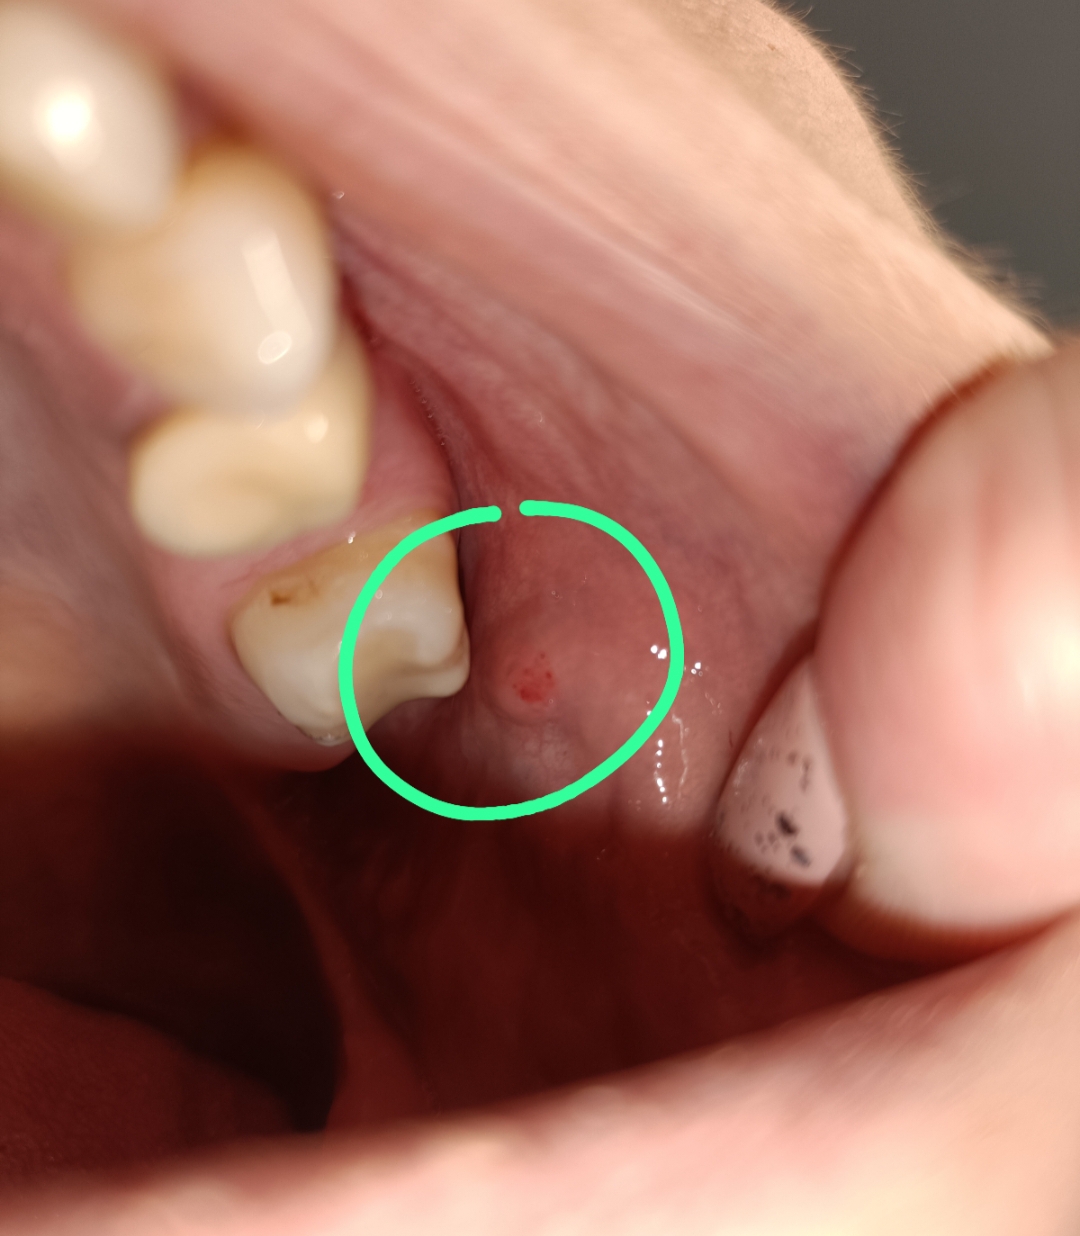

Dejdy ha iniziato il topic Macchie sulla gengiva nel forum Problemi in generale